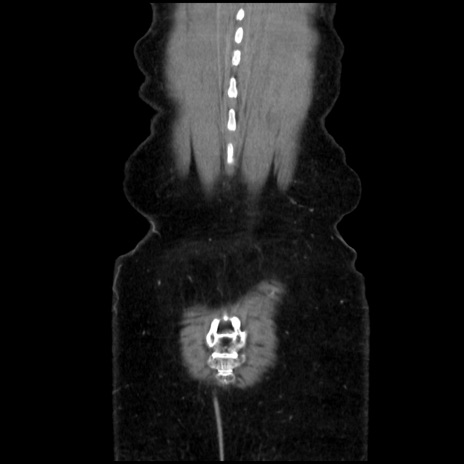

症例32(冠状断像)

症例

【症例】40歳代 女性

【主訴】上腹部痛、嘔気・嘔吐

【現病歴】約9時間前頃から急に上腹部痛、嘔気、嘔吐が出現。改善しないため救急要請。

【既往歴】子宮頚癌(広汎子宮全摘術、放射線療法)、腸閉塞

【身体所見】腹部:平坦、軟、腸雑音亢進、上腹部を中心に腹部全体に圧痛あり。

【データ】WBC 8400、CRP 0.03